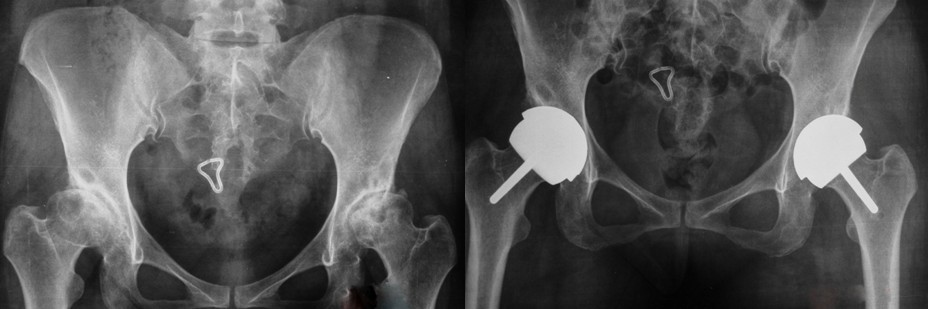

摘要 目的 探讨年轻髋关节患者行髋关节置换内固定的选择,为临床治疗提供依据 方法 选择年龄55岁以下需行全髋关节置换的患者14例,进行随访研究,手术所用的假体全部为Conserve Plus假体结果 全部14侧均进行随访,没有发生髋关节脱位,没有发生股骨颈骨折,也没有发生感染和其它并发症,病人的Harris评分由术前的40分提高到94分,临床效果显著 结论 全髋关节表面置换术对于年纪轻,又需行髋关节置换的患者是一种较好的选择方式,不影响二次髋关节翻修的效果,也不增加二次髋关节翻修的难度.

年轻患者患髋关节疾患需要行髋关节置换一直是骨科面临的一个难题,髋关节术后其解剖和生物力学功能的保留和恢复是我们追求的手术目标,而新一代全髋关节表面置换术具有上述的优点,同时不影响以后的翻修效果,对于年轻患者来说,选择这种手术更为合适,从2005-2008年应用Conserve Plus 髋关节表面假体行人工髋关节表面置换14例18侧,取得了良好疗效,现报告如下

结果 所有的病侧均进行了超过6个月的随访,术前后均进行Harris评分,即优90-100良80-90尚可70-90差<70.术前均分为35分.术后均分为94分,所有病人均没有股骨头骨折,髋关节脱位和感染.X线检查没有发现骨质溶解和骨缺损.评价:优6例,良1例,一般1例,.